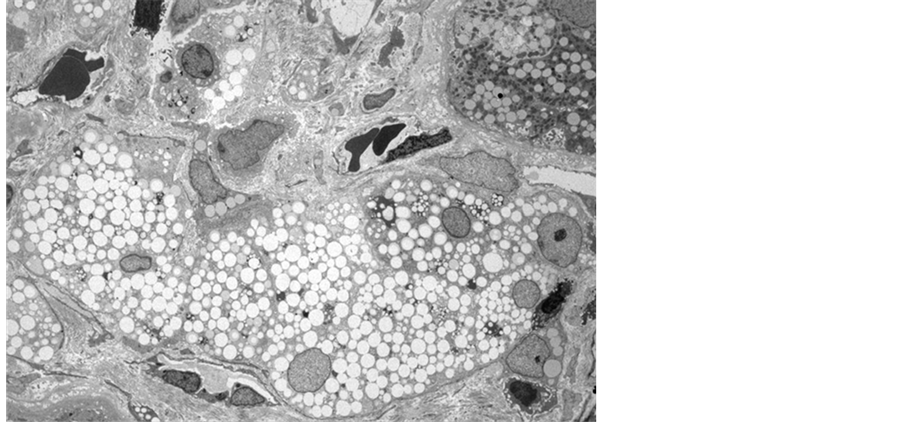

A 12-year-old girl presented with puffy face, bilateral lower-leg edema and frothy urine in recent two months. Biochemical studies showed nephrotic range proteinuria, hematuria > 30 erythrocytes per high-power field, lipiduria, serum cholesterol 10.1 mmol/l, albumin 16 g/l, and creatinine 30.5 mmol/l. Her blood pressure was 108/70 mmHg, and renin-angiotensin system blockers were not used. A kidney biopsy was performed for her nephrotic-nephritic syndrome with unclear etiology. Light microscopic examination with hematoxylin and eosin stain revealed rigidity and moderate thickening of the glomerular basement membrane (GBM), and segmental glomerular sclerosis. Accumulating an excessive amount of neutral fats in renal tubular cells led to extremely foamy appearance and luminal obliteration (Figure 1). Such fatty change is followed by necrosis of injured cells and detachement from the basement membranes compounding luminal obliteration. Electron microscopy depicted irregular distribution of GBM with basket-weave appearance (thinning, thickening, splitting and lamination of lamina densa) and diffuse effacement of podocyte foot processes (Figure 2). Myriad intracellular lipid droplets were noted within tubulointerstitial lipid-laden foamy macrophages (Figure 3).

Figure 3. Myriad intracellular lipid droplets were noted within tubulointerstitial lipid-laden foamy macrophages.